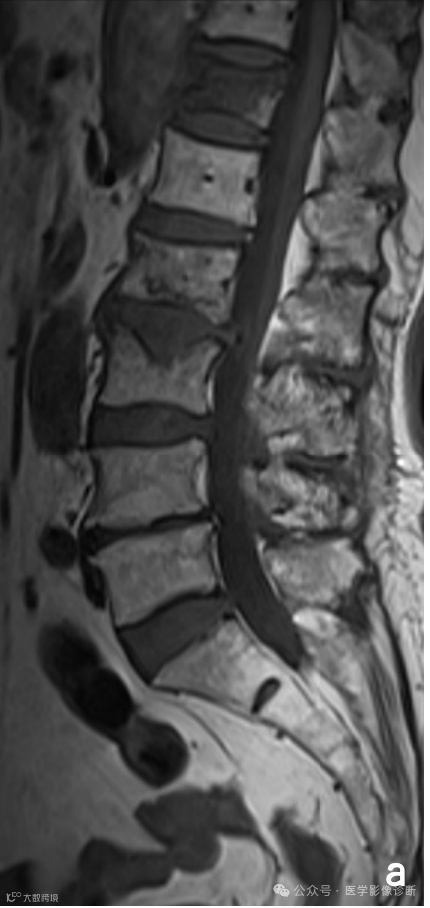

Case 1

患者,女性,81岁,淋巴瘤化疗后腰痛一周。

影像学表现

腰椎MRI扫描T1WI(A)和T2WI/FS(B)显示多个椎体多发异常信号伴轻度压缩骨折,受恶性肿瘤病史影响放射科医生将其诊断为转移瘤,而遗漏了终版下条带样低信号等良性压缩骨折的征象,患者行椎体活检并成形术后(C),术后病理证实无肿瘤迹象。